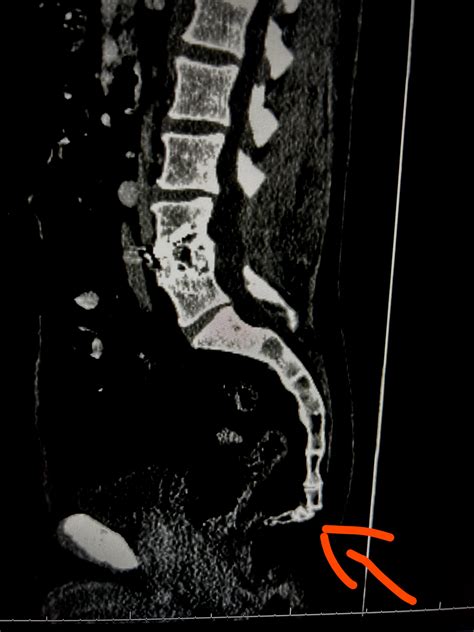

• CT scans: CT scans provide detailed images of the tailbone and surrounding structures, helping to identify fractures, dislocations, or other abnormalities.